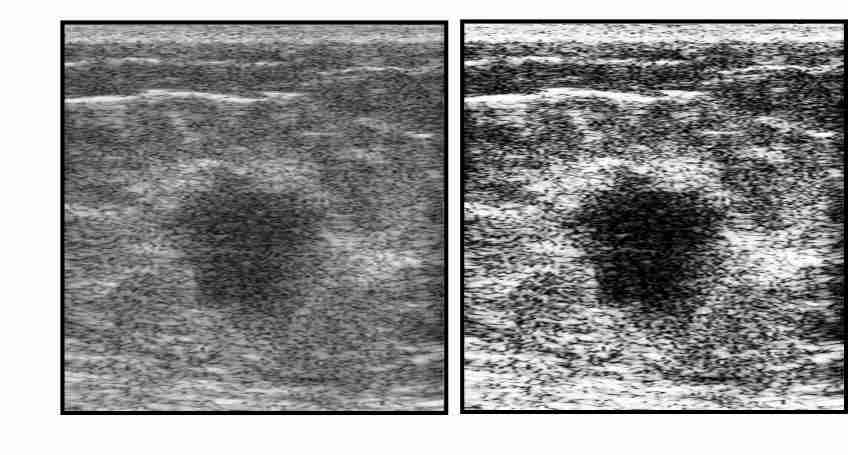

Invasive ductal carcinomas generally have fuzzy borders as a result of having invading margins. On the contrary, cancers that elicit little desmoplastic reaction (proliferation of fibroblasts) typically have clear margins, but are highly irregular in shape. We define Margin Definition as the sum of the magnitude of the gradient of M𝑀M on a lesion contour normalized by the sum of magnitude of M𝑀M on the lesion contour [33]. Although this feature uses both the lesion contour as well as a spectral parameter, we used this as a spectral feature. As M𝑀M is statistically well-behaved, is relatively speckle-free, and can more easily be corrected for system effects and diffraction, the midband fit image was used instead of the B-mode (envelope of RF echoes) image. Benign lesions exhibit greater value of gradient-based margin definition. Figure 3.2 shows two lesion images with sharp & fuzzy borders and shows their gradient images that are used for calculating margin definition. The lesion with sharp border gives the value of 0.28980.28980.2898 and the lesion with fuzzy border gives the value of 0.02650.02650.0265.

Refer to caption

Figure 3.2: (a),(d): Original images, (b),(e): Gradient images, (c),(f): Mask for margin definition calculation.